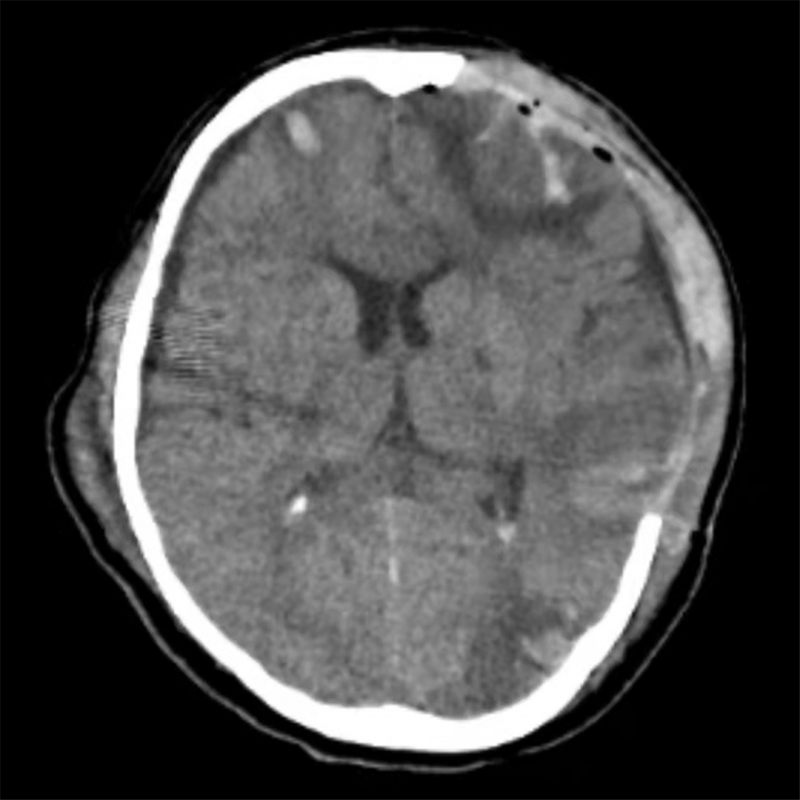

术后颅脑CT示:颅内血肿清除完全,中线结构回归。